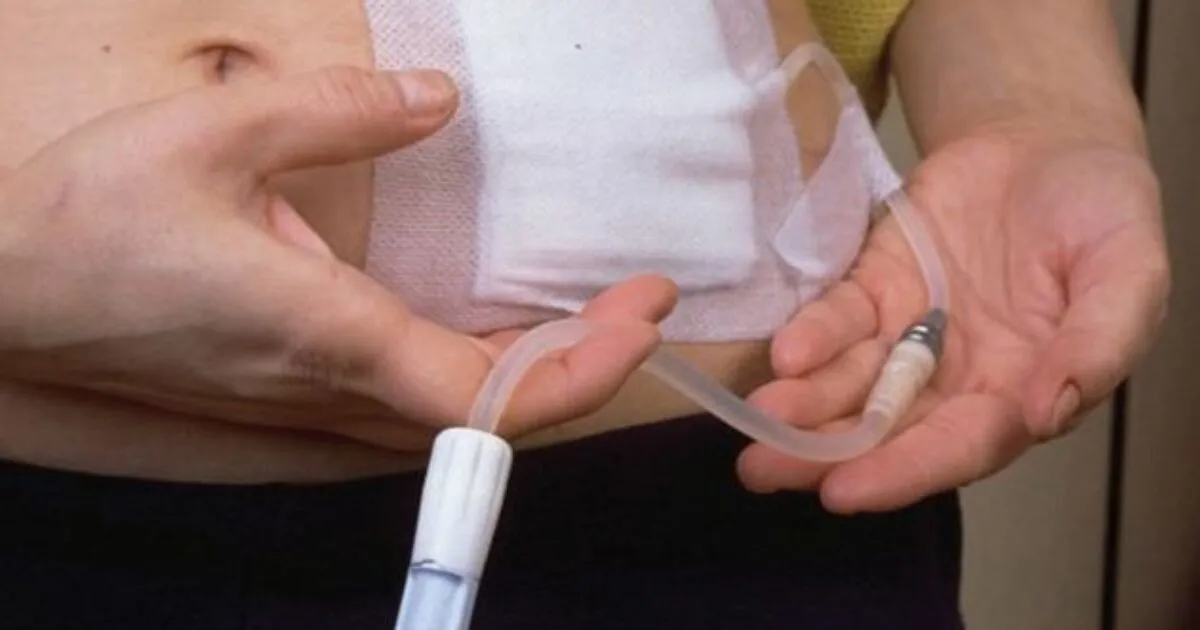

A DRPAD não é contraindicação à DP — e, na prática, muitos pacientes têm resultados comparáveis à hemodiálise. O “porém” está na mecânica: rins/hepatomegalia podem reduzir tolerância a volumes, aumentar risco de hérnias e extravasamentos, e piorar desconforto respiratório. Com técnica adequada (cateter presternal ou lateral, volumes menores, cicladora noturna e decúbito supino), a maioria das barreiras é contornável. Neste post, revisamos quando a DP é ótima, quando exigir cautela e como ajustar a prescrição para segurança e qualidade de vida.